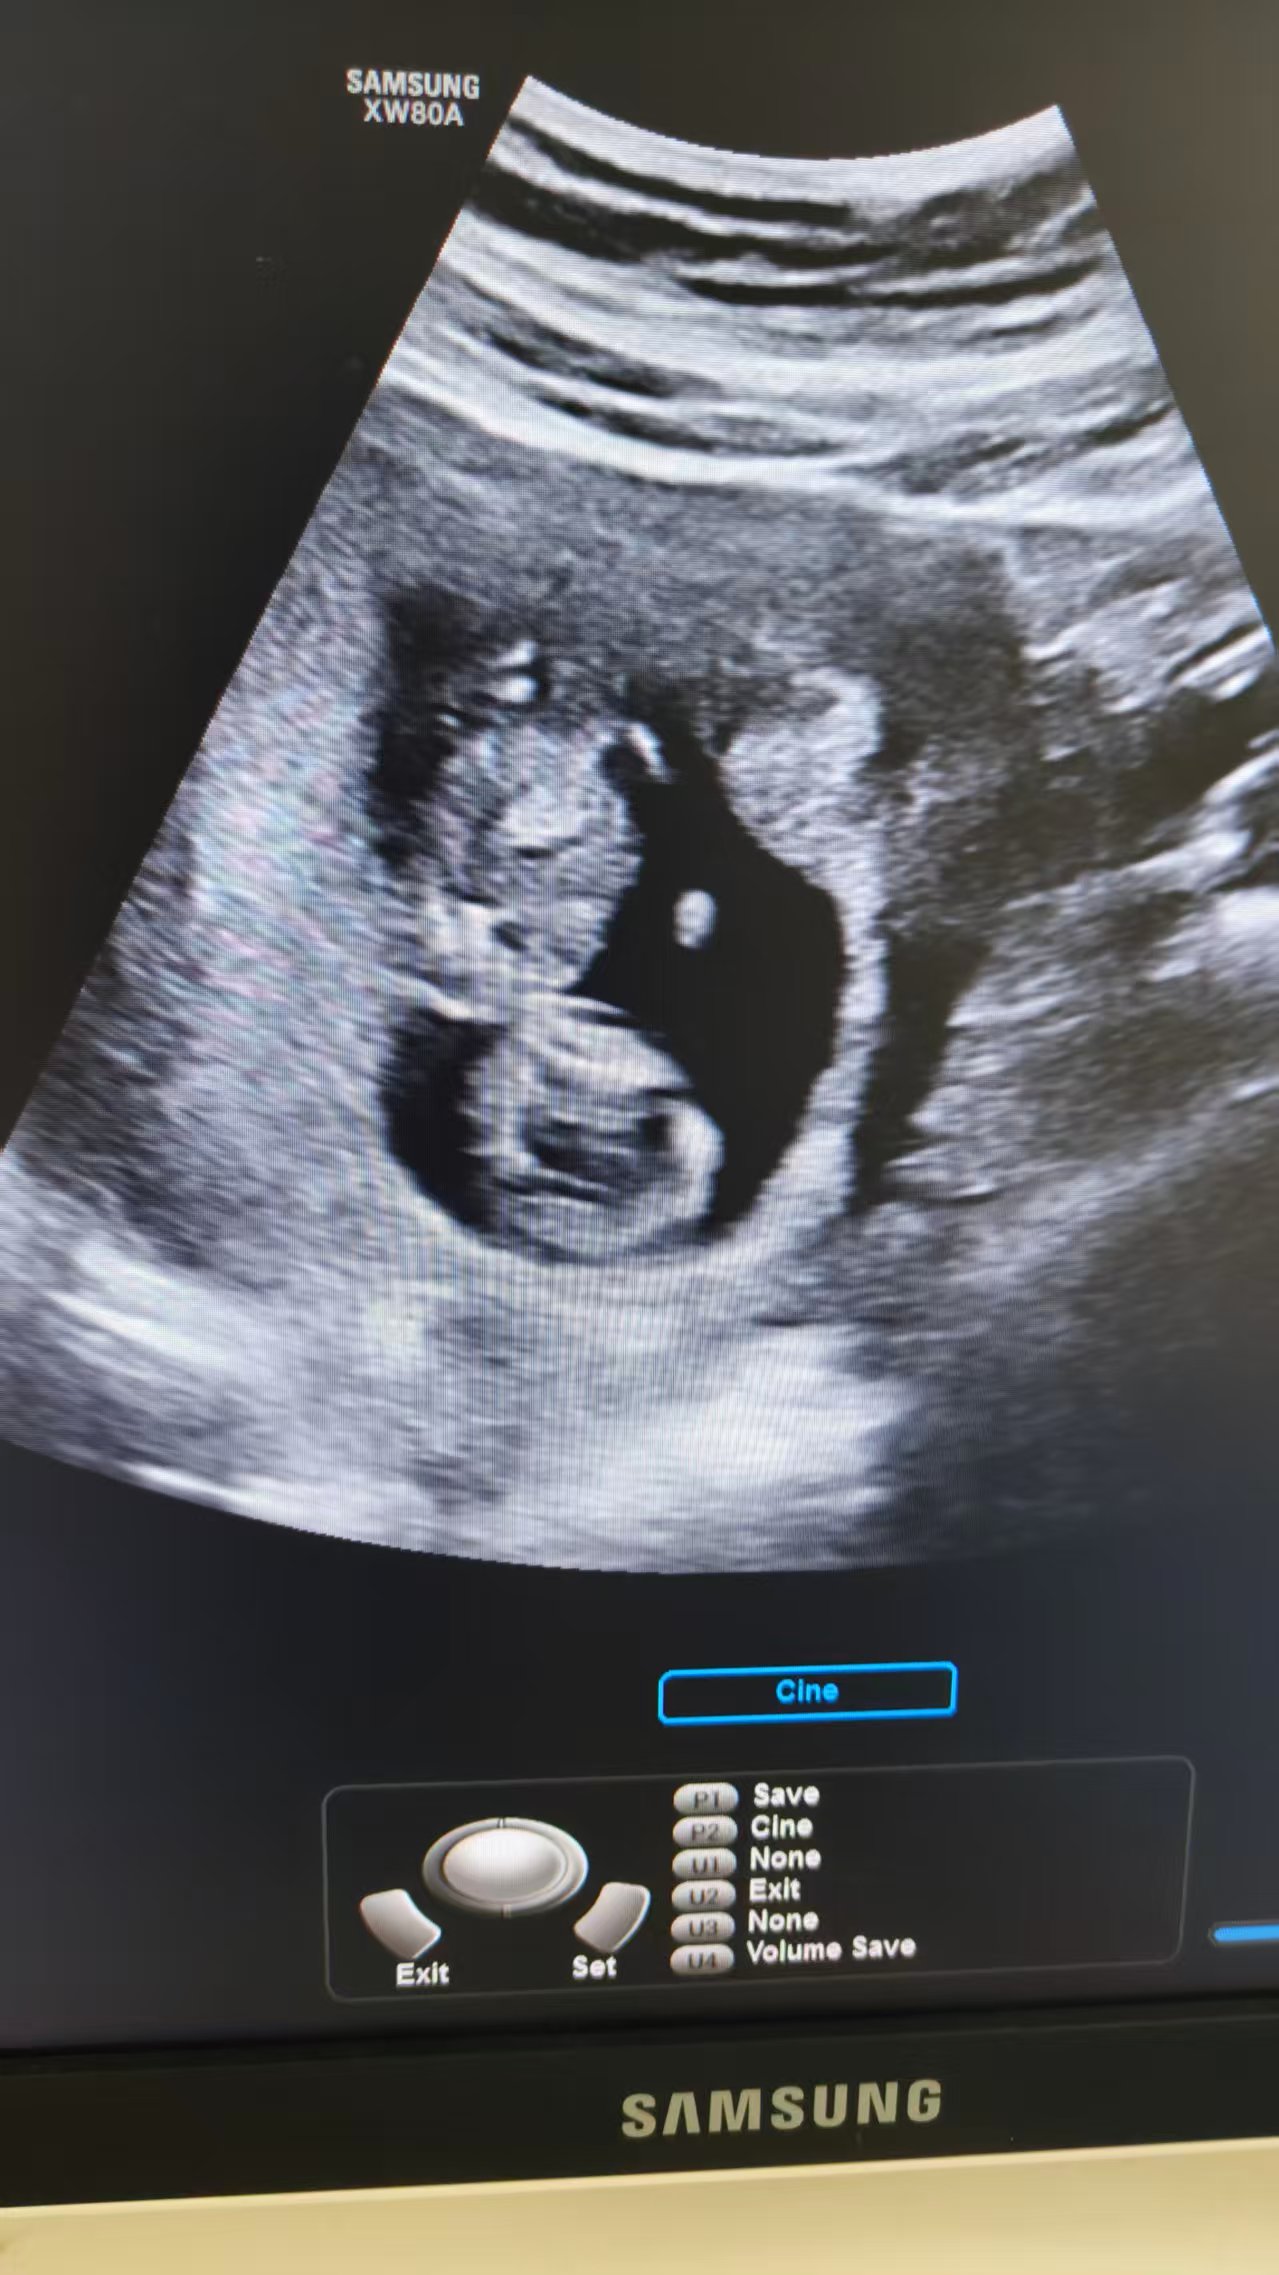

NT检查的曲折经历

今天去做NT检查真是波折不断啊!宝宝位置一直不好,第一次倒着睡,第二次又背对着,来来回回折腾了4次都没成功。医生让我出来重新排号,等三个人再进去检查。

最难受的是医生不让先抽血,说要等NT过了才能抽,饿得我头晕眼花的。群里姐妹建议喝脉动、吃巧克力,可是医生不让进食,连水都不敢喝。下午继续检查时,宝宝还是不配合,我都怀疑她是不是睡着了[捂脸]。

最后实在没办法,只能明天再去检查了。姐妹们有没有什么让宝宝配合的小妙招啊?我现在是又饿又累,整个人都麻了[苦涩]